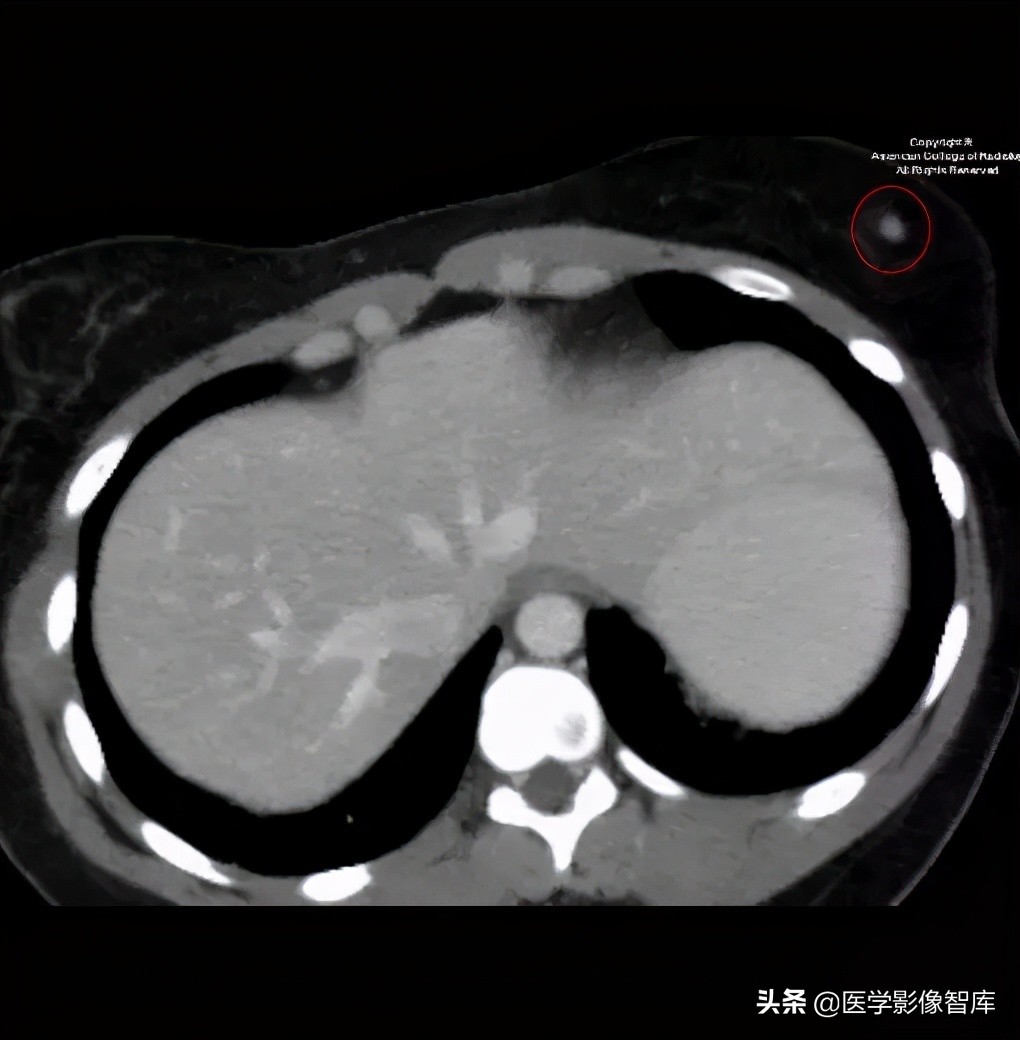

图 3. 轴位 CT 显示左侧乳房偶发的良性肿块(红色圆圈)